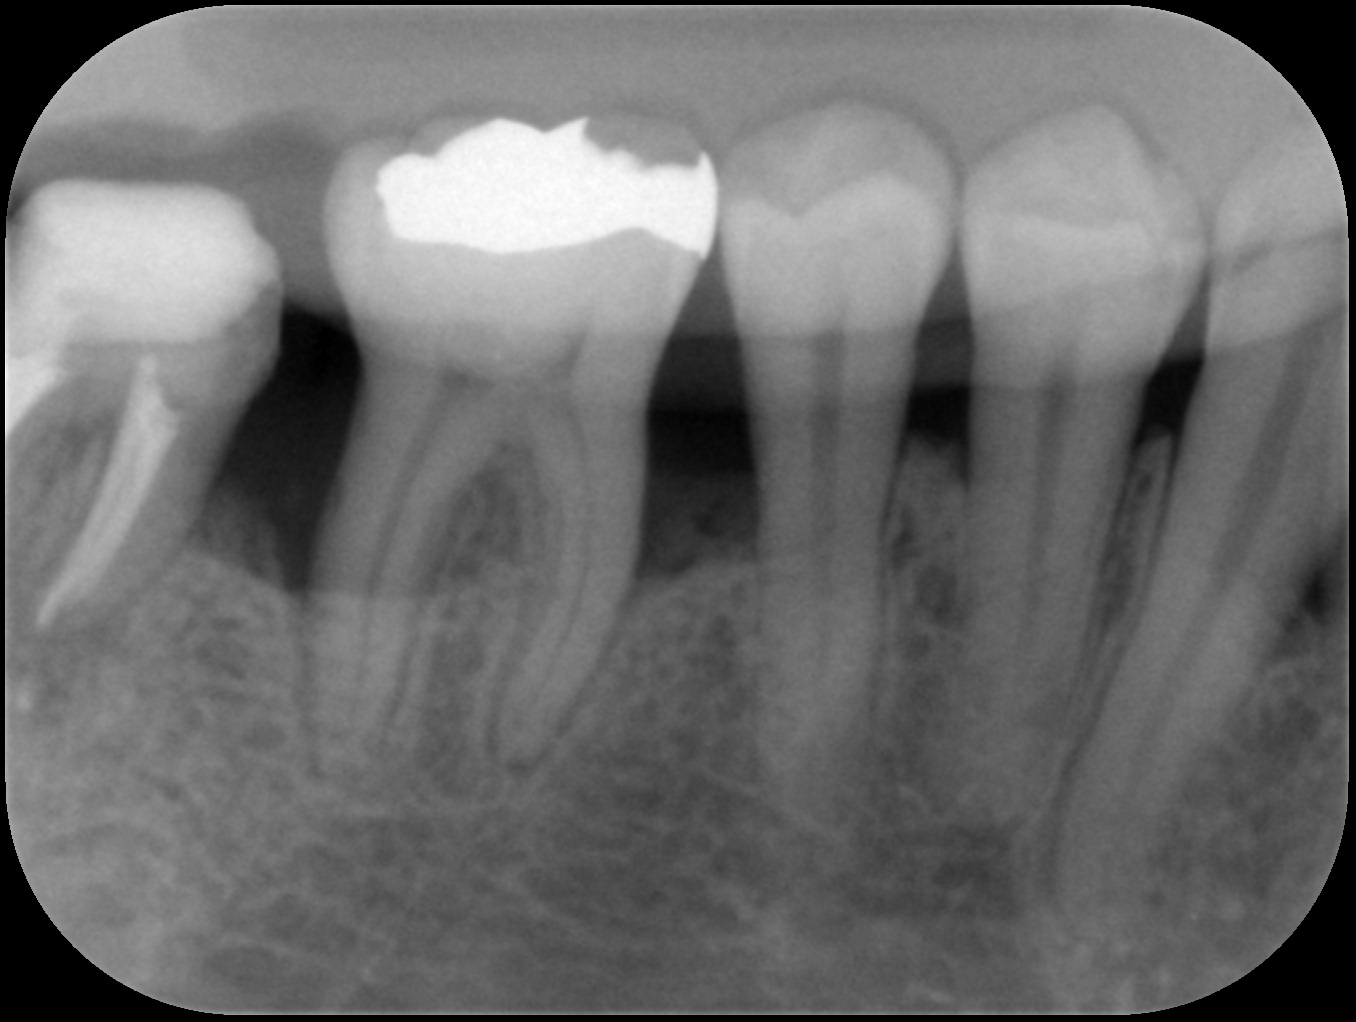

初診時

歯周基本治療後

歯周組織再生療法後6ヶ月

| 主訴 | 他院にて歯周病と診断され、抜歯するしかないと言われたが年齢的(初診時30代)に抜歯はしたくない。 歯周病の専門医に相談した方がいいと言われ当院を受診。 |

| 治療内容 | 精密検査の結果、歯周ポケット(歯と歯茎の間の溝)4mm以上の部位が全体の67%、最大11mmの歯周ポケットを認めた。*歯周ポケットの正常値は3mm以下。 またエックス線画像からは奥歯を中心に歯槽骨(歯を支える骨)の著しい吸収を認めた。 ブラッシング指導、歯肉縁上歯石の除去、歯肉縁下歯石の除去、根管治療を行った後、再評価検査を行った結果、全顎的に歯周外科治療が必要であったため歯周組織再生療法を行った。 |

| 治療期間 | 9ヶ月 歯周基本治療(2ヶ月) 歯周外科治療、歯周組織再生療法(2ヶ月) 歯周組織再生療法後は6ヶ月経過を確認しメインテナンスへ |

| 費用 | 歯周組織再生療法(サイトカイン+骨補填剤の併用療法) 165,000(1部位につき) |

| リスク・副作用 | サイトカインと骨補填剤を併用した歯周組織再生療法では術後の腫れや痛みを生じる場合があります。 歯周組織(特に歯槽骨)の再生が認められた後も定期的なメインテナンスやご自身でもブラッシングが大切です。それを怠ると再発や悪化につながりますのでご注意ください。 *当院ではブラッシング指導を徹底し、ご自身できちんと口腔内環境を管理できるようご協力いただいております。ブラッシング状況が改善されない場合は歯周外科治療へ進まないこともありますのでご理解ください。 |